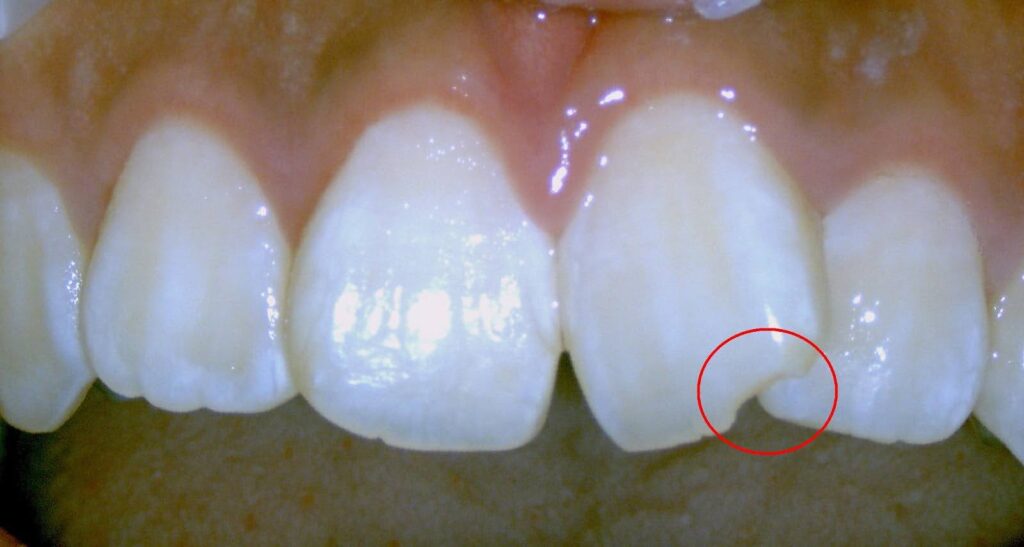

赤丸が膿んでいる病変部